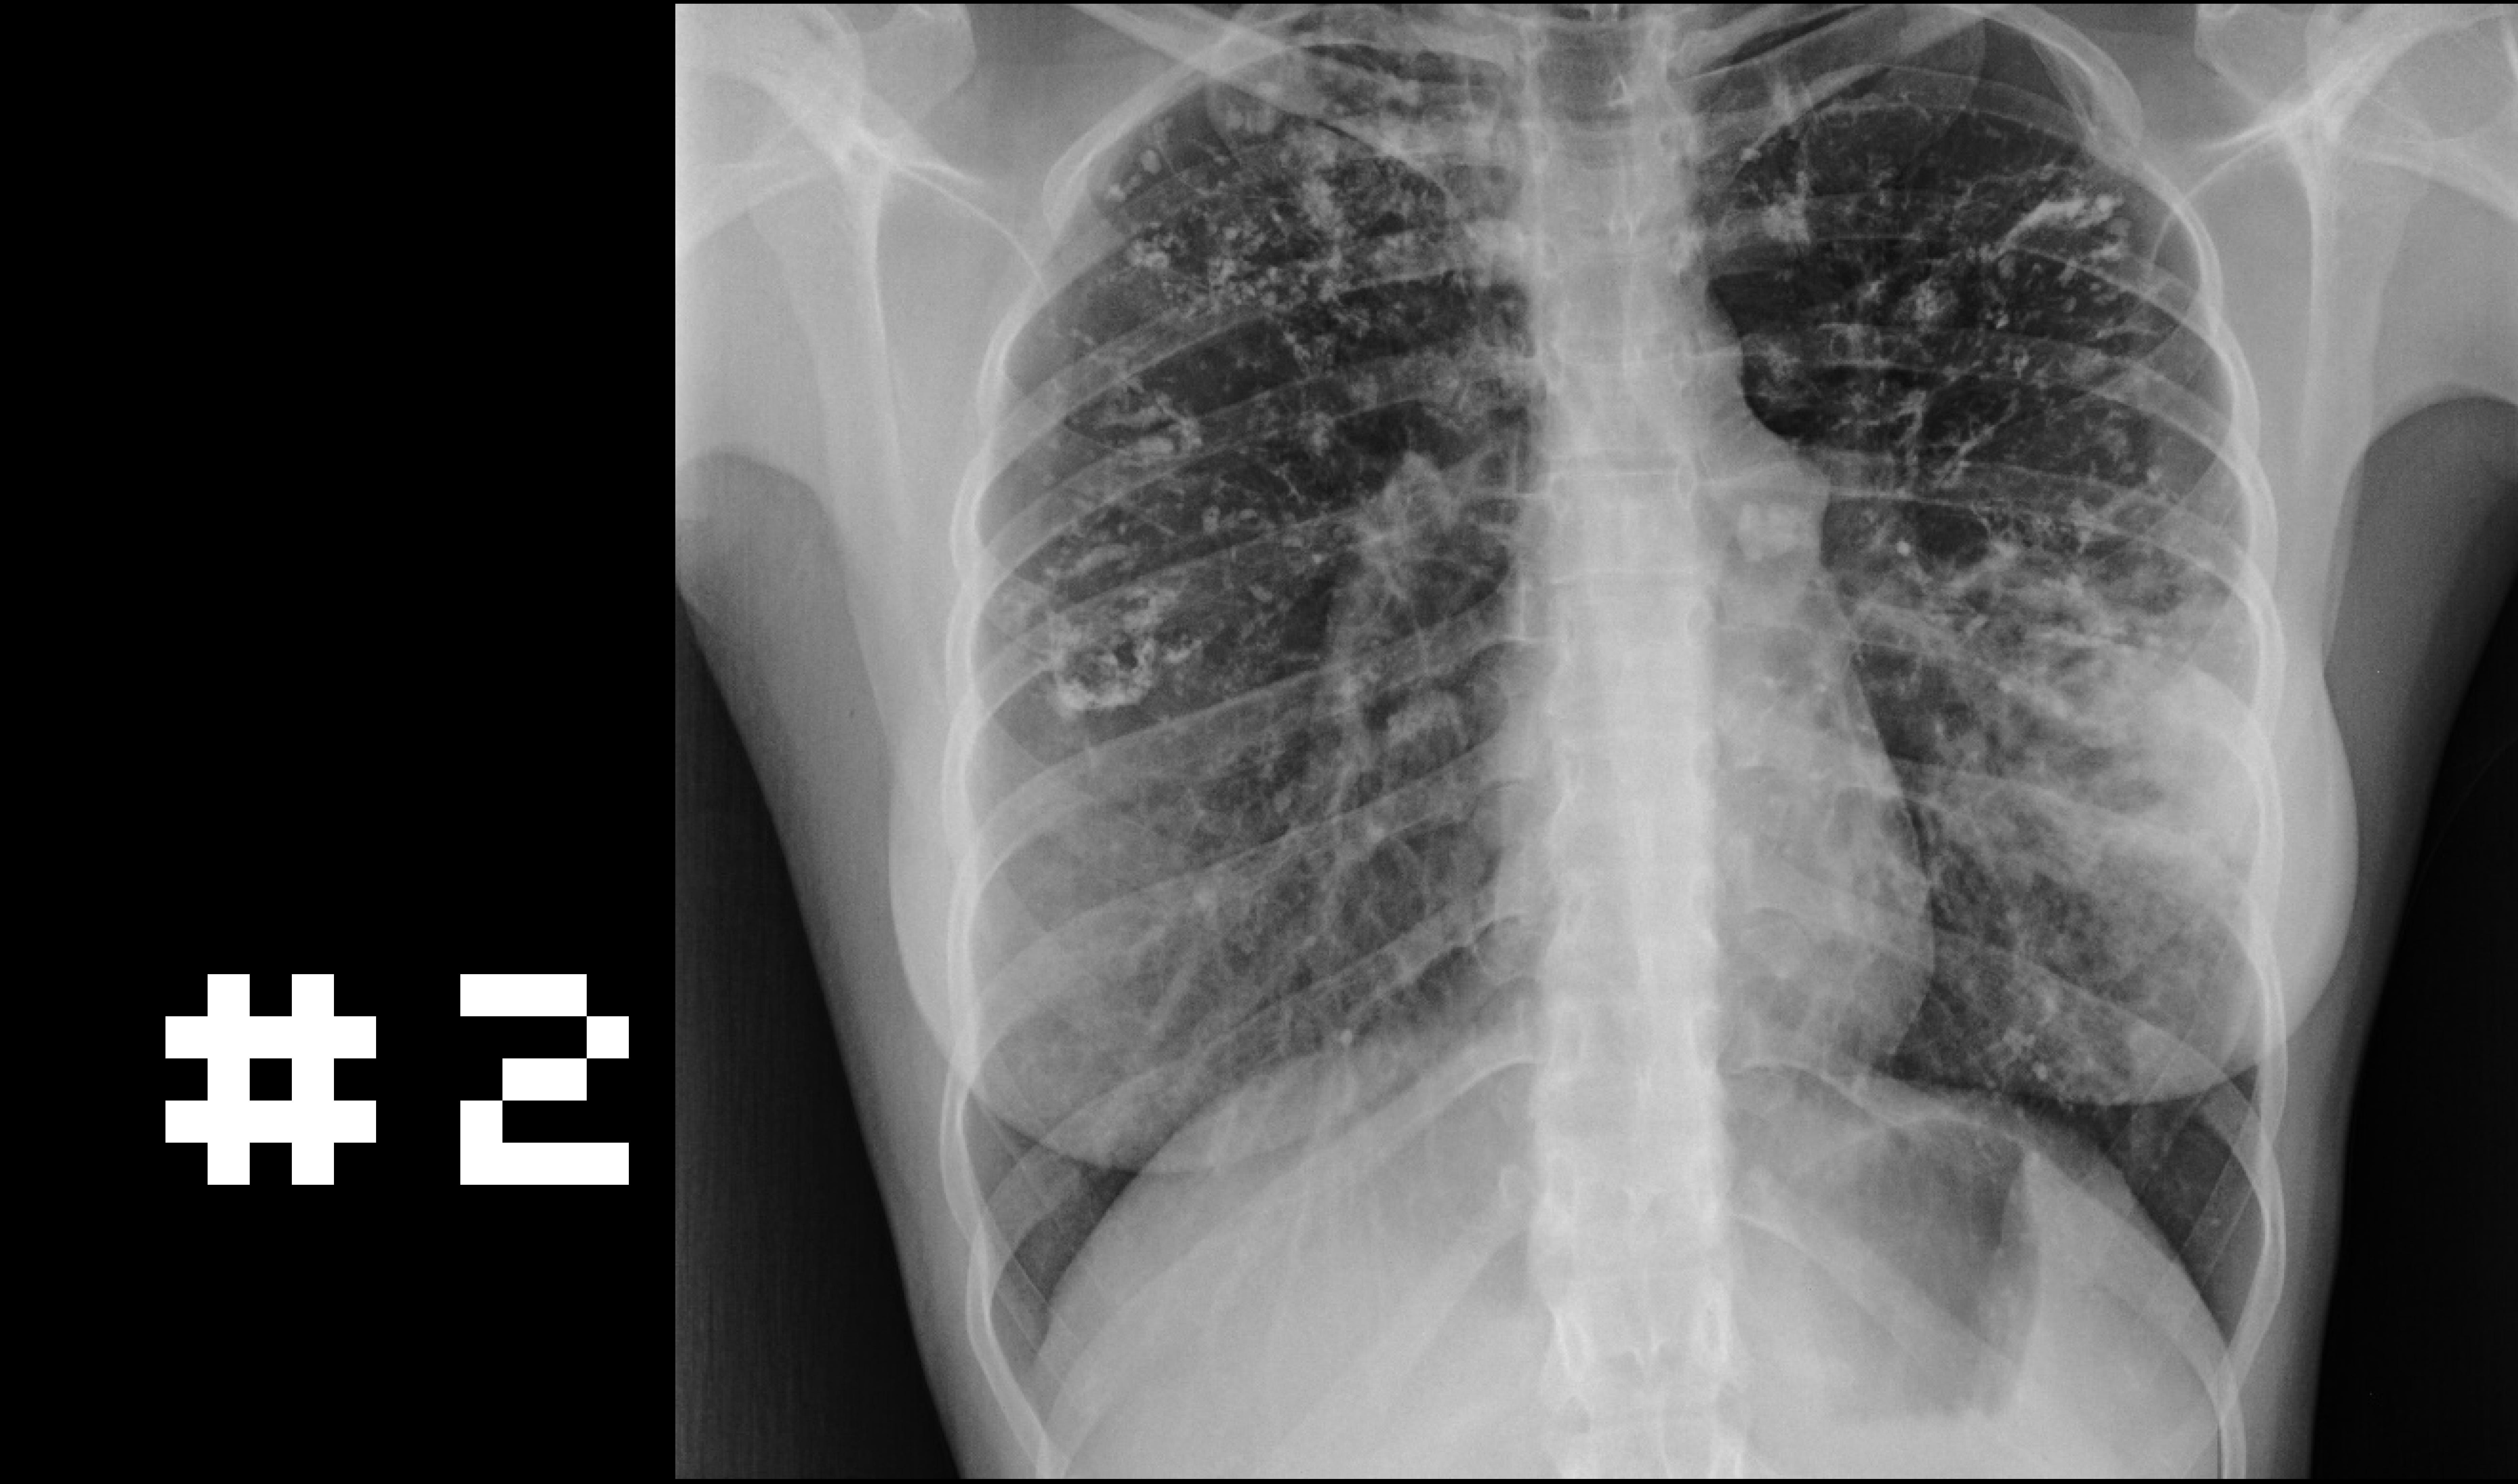

Other Classic symptoms

Chronic cough

Weight loss

Night sweats

Fever

Haemoptysis

Treatment requires months of multiple antibiotics, which is why presentation, investigations and treatment adherence are critical.